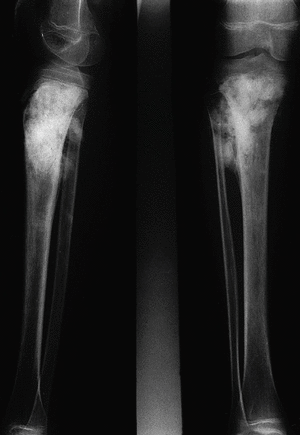

En la segunda placa (fig. 2) tomada seis meses después, se objetiva un franco avance de la lesión: el área de esclerosis atraviesa ya la placa metafisaria, extendiéndose también hacia la diáfisis. Existen lesiones líticas destructivas más evidentes en el borde medial de la tibia, perdiéndose en algunas zonas la continuidad de la cortical. Se ve un importante crecimiento de la masa de partes blandas con áreas de osificación.